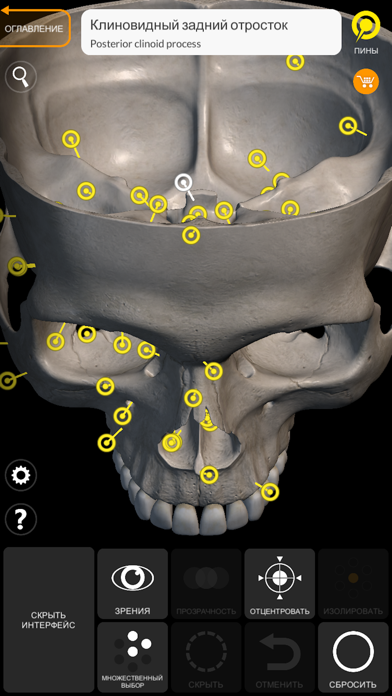

Скриншоты